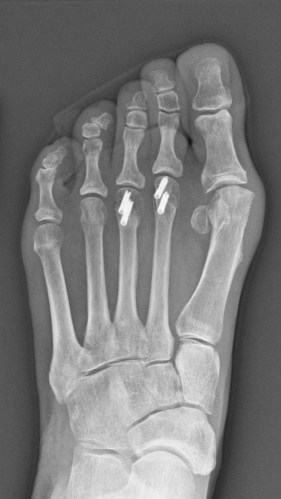

Total Bill: $115,527 for a three-day hospital stay, including $15,076 for four tiny screws — measuring 2.8 millimeters wide and no more than 14 millimeters long — placed in the two middle toes of her left foot.

Medical Treatment: Young underwent two operations on the same day in June 2017. One surgeon addressed an injury in Young’s shoulder, caused by arthritis and overuse. A second surgeon performed several procedures on her foot, including removing a bone spur. To better align Young’s middle toes, the doctor removed a slice of bone from the center of each toe, and then reconnected the two ends with surgical screws made by Arthrex, a medical device manufacturer based in Naples, Fla.

Clearly, the screws used in Young’s surgery are more sophisticated than those sold at the local hardware store. Many of the screws in Arthrex’s online catalog are made of titanium, which is popular for surgery because it’s strong and durable. The screws are also hollow, designed to fit over a guidewire so that doctors can place them in precisely the right place.